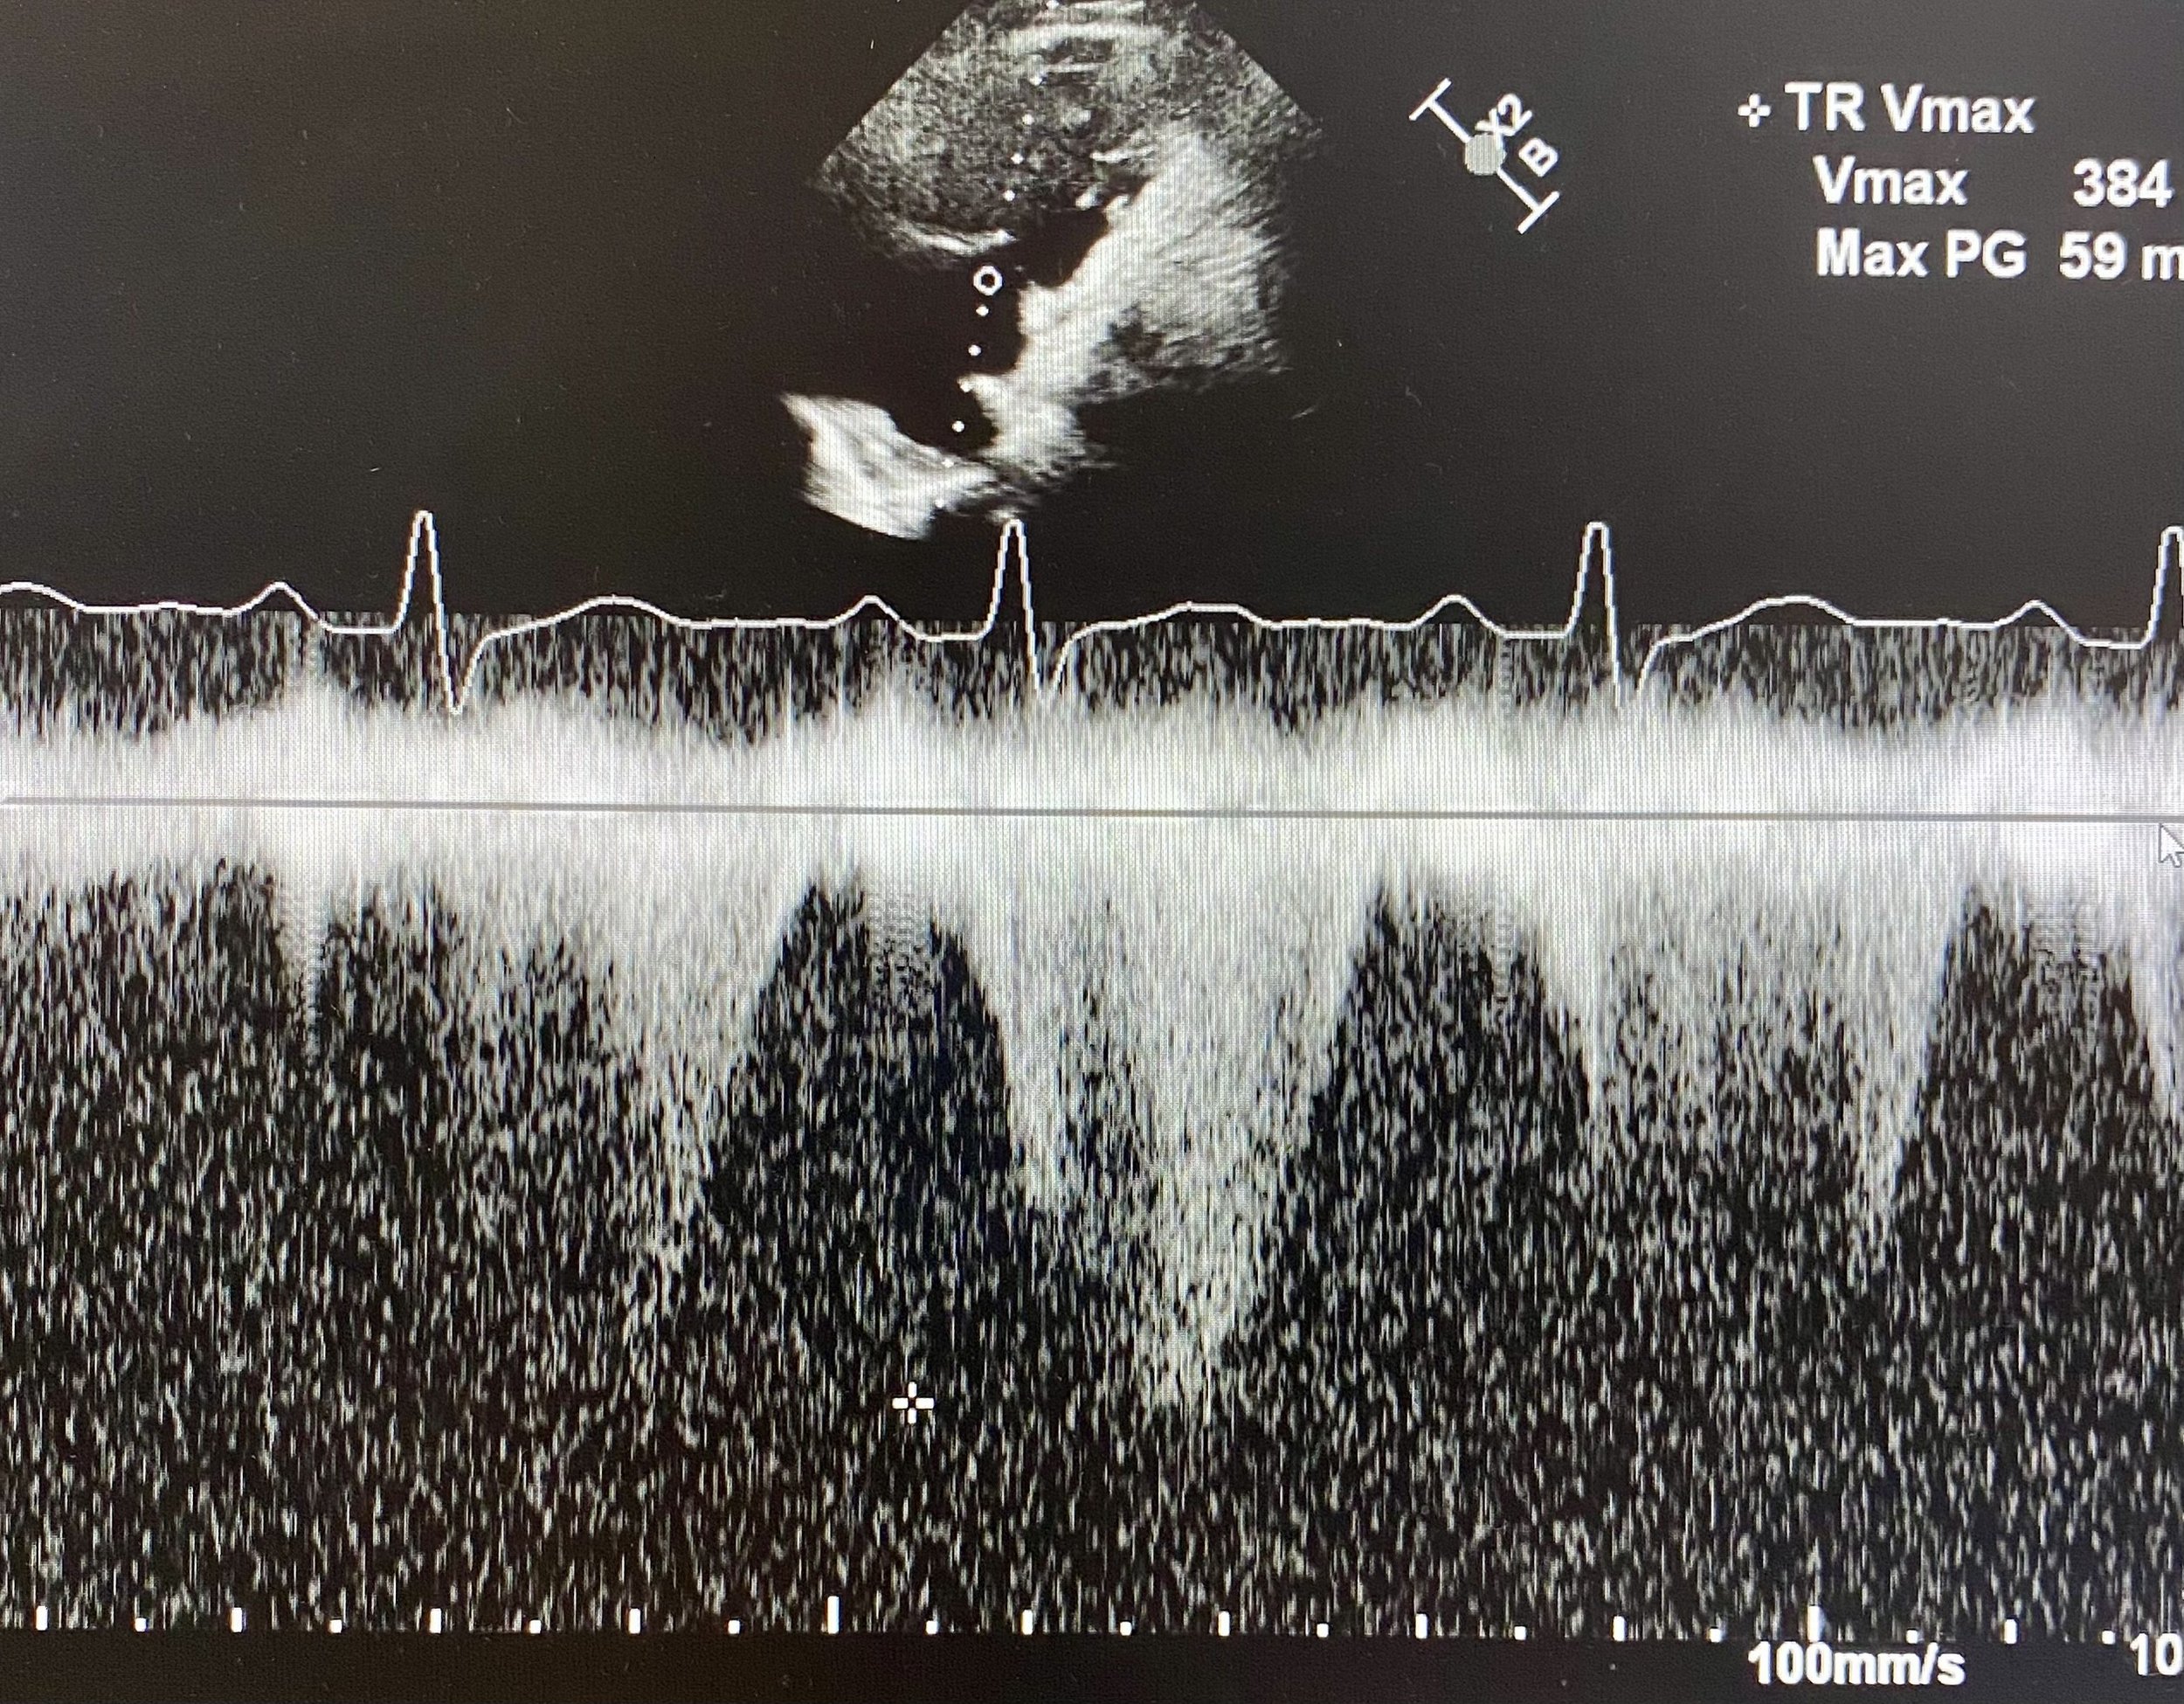

Quantifying pulmonary pressures with the use of doppler is key to many right-heart pathologies. Measuring PASP (Pulmonary Artery Systolic Pressure) is a two-step process.

i) Measure RVSP (RV Systolic Pressure) which is the pressure difference between the RV and the right atrium. To calculate this identify the tricuspid regurgitation jet using colour doppler. This is usually done from an Apical 4-Chamber view. Here you can move the probe medially can get a better TR jet (although it will obliquely cut the RV making it looking larger than it is in 2D). Once the TR jet is identified put CW Doppler through the jet. A good doppler signal will be a symmetrical parabola (see below). The apex of the parabola is the TR Vmax, and the US machine can use this to calculate the RVSP in mmHg (equation is RVSP = 4 x (TR Vmax)^2)

In this patient assessment of the TR jet showed RVSP of 59mmHg (see cross and automatic calculation by machine) which is severely elevated. The RAP was estimated to be around 8 giving a PASP of 67mmHg.

This is severely elevated pulmonary pressures supporting the diagnosis of acute PE with significant obstructive effects on the right heart.